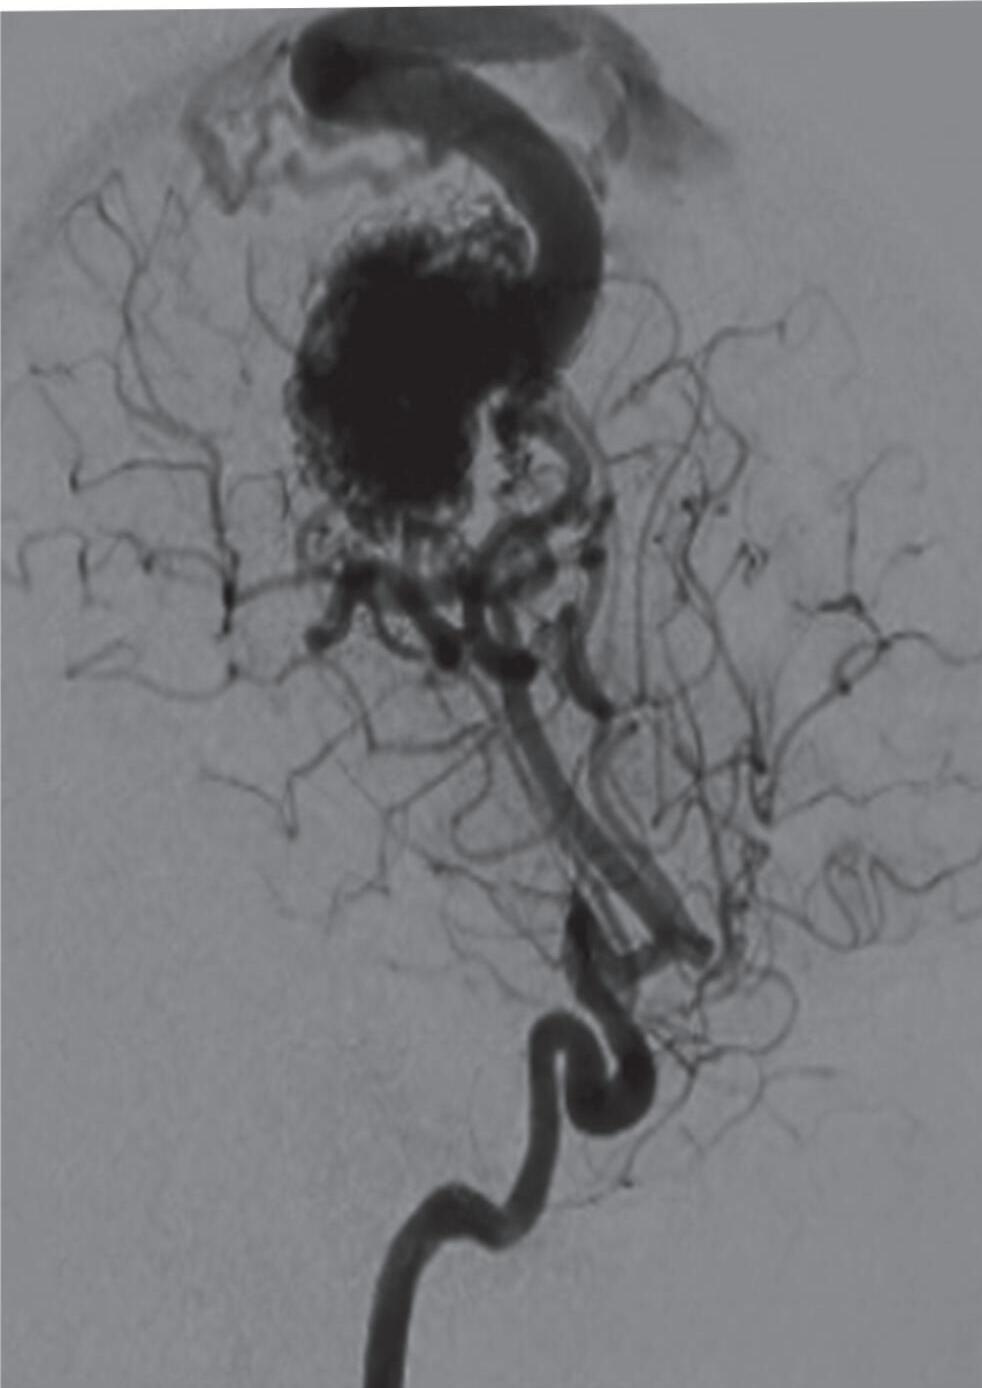

A soma dos pontos de cada um desses três critérios resulta em uma pontuação total, que ajuda a determinar a gravidade da MAV e, assim, a abordagem terapêutica a ser instituída. Cada grupo da classificação de Spetzler-Martin demonstra graus variáveis de risco e complexidade, com implicações diretas na escolha do tratamento. A seguir, exemplos de cada um dos cinco graus desta classificação: grau 1 (Fig. 1-13), grau 2 (Fig. 1-14), grau 3 (Fig. 1-15), grau 4 (Fig. 1-16), grau 5 (Fig. 1-17). A classificação de EM pode gerar uma combinação de resultados e ser utilizada para nortear o tratamento. Apesar de ter sido, na época, um grande avanço na avaliação e no tratamento das MAVs cerebrais, a classificação de Spetzler-Martin necessitou ser modificada, em virtude dos avanços no diagnóstico e no tratamento dessas lesões. Em 2010, Lawton propôs essa mudança objetivando facilitar mais ainda a tomada de decisão terapêutica das MAVs.28 Assim, o novo sistema possibilita uma melhor análise do padrão de drenagem venosa, por exemplo. Então, com base nesse critério, malformações de pequeno tamanho localizadas em áreas não eloquentes, com drenagem venosa profunda, são mais complexas de tratar do que as MAVs grandes, localizadas em áreas eloquentes, porém sem comprometimento da drenagem venosa ou que apresentem um sistema de drenagem

Fig. 1-15. RNM encéfalo T1 (a) sagital sem contraste e (b) axial com contraste demonstrando MAV grau 3, parcialmente embolizada, localizada no giro temporal superior e lobo parietal direito. (c) Arteriografia cerebral em perfil, demonstrando a irrigação pelos ramos da artéria cerebral média e posterior, com drenagem superficial nas veias de Labbé até o seio sigmoide, e o complexo de Trolard no seio sagital superior. O nidus da MAV está demonstrado pelas setas azuis grandes e a drenagem venosa pelas pontas de setas.

Fig. 1-16. RNM encéfalo T1 com contraste: (a) Coronal e (b) axial demonstrando MAV grau 4 frontoparietal esquerda. (c,d) Arteriografia cerebral AP mostrando a irrigação pelos ramos da cerebral anterior e média esquerda, além da cerebral anterior direita, com drenagem superficial para o seio sagital superior. Seta azul apontando para o nidus da MAV.